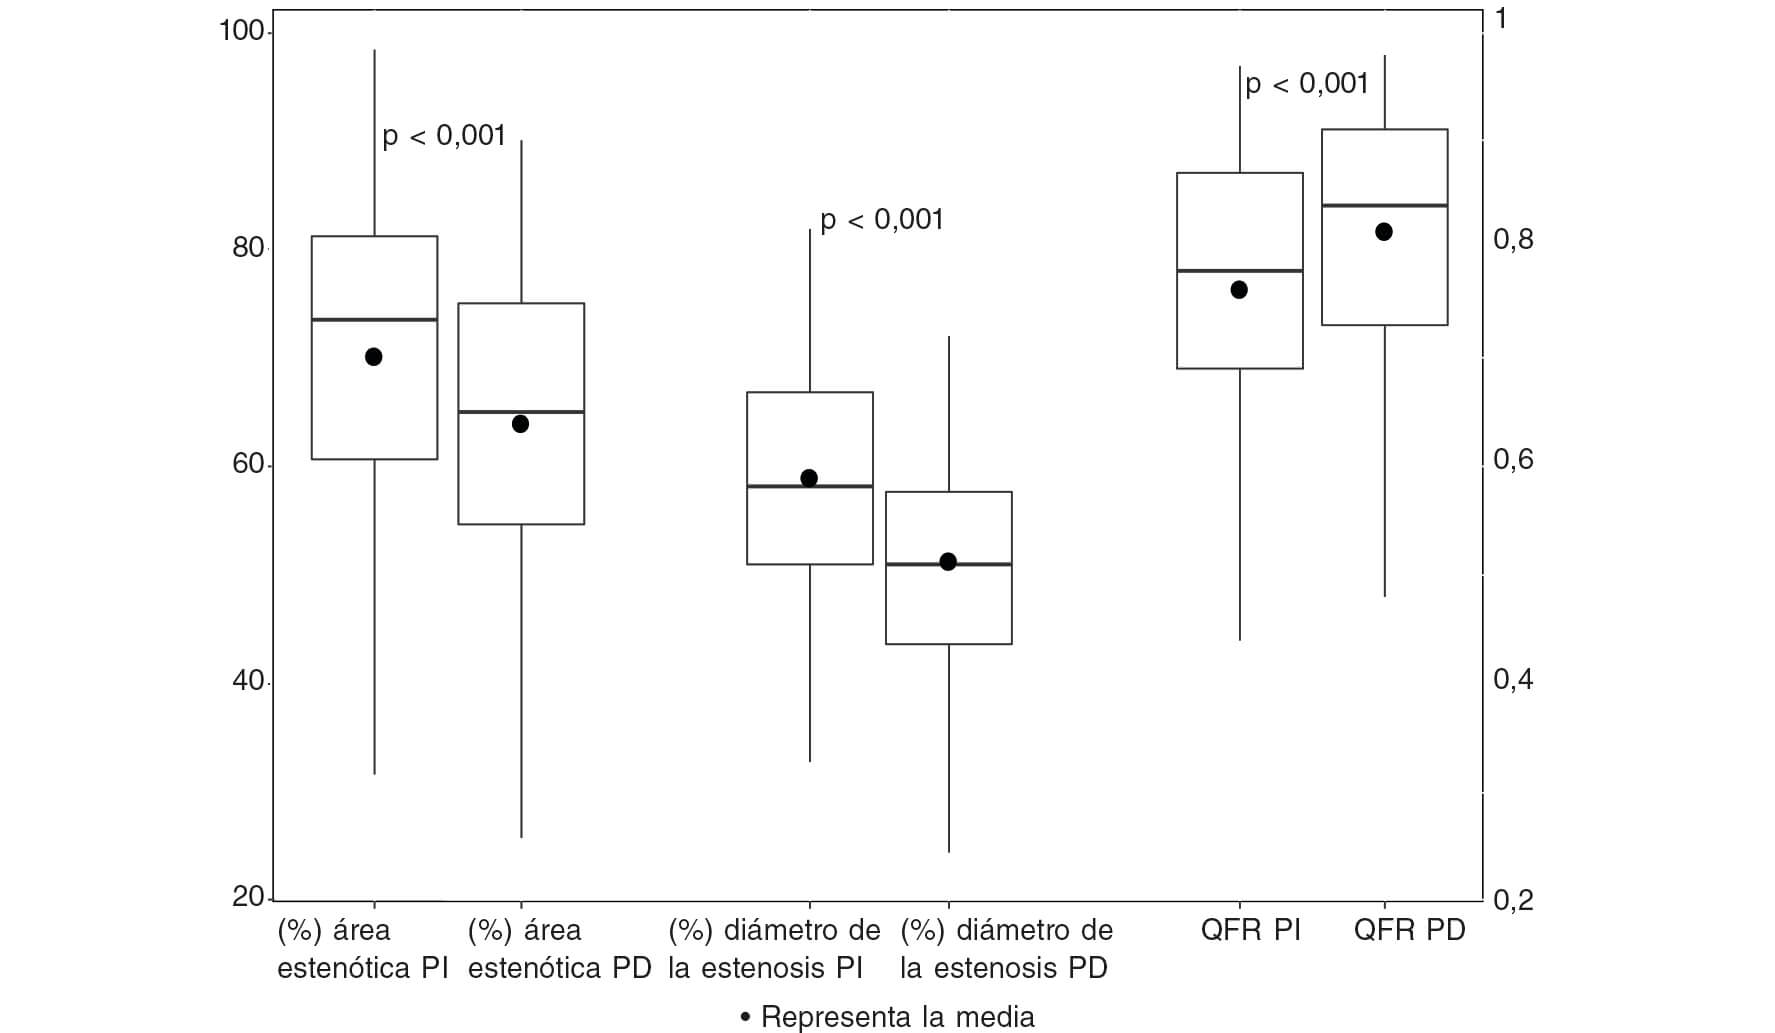

Cambios QFR a lo largo de los procedimientos índice y diferido

Ciento veintidós (93,1%) de las 131 lesiones en vasos no causantes se consideraron aptas para ser sometidas a revascularizaciones percutáneas programadas según valoración visual de la angiografía. De estas, solo el 56,3% arrojaron valores QFR ≤ 0,80 en el procedimiento índice cuando se valoraron retrospectivamente (figura 3). Se pudo confirmar una caída sin relevancia estadística de los valores QFR entre el procedimiento índice y el diferido en pacientes con valores QFR iniciales > 0,80; no obstante, 2 pacientes con valores QFR inicialmente irrelevantes experimentaron una caída < 0,80 en la valoración de la angiografía diferida. Todos los pacientes con valores iniciales > 0,82 confirmaron la presencia de estenosis en el segundo procedimiento. Por otro lado, el 45,9% de las lesiones con valores QFR significativos fueron consideradas irrelevantes cuando fueron valoradas durante el segundo procedimiento, con diámetros medios y áreas estenóticas más grandes (p < 0,001 para ambos) tal y como revela la tabla 2. Los principales cambios observados entre ambos procedimientos se muestran en la figura 4 y en el ejemplo paradigmático de la figura 5. La sensibilidad y especificidad de valores QFR > 0,82 durante el procedimiento índice para predecir estenosis importantes (QFR < 0,80) durante el procedimiento programado fueron del 84 y 58,7%, respectivamente, con un valor predictivo positivo del 52,5% y un valor predictivo negativo del 87% (figura 6). La estrategia terapéutica se implementó con independencia de los hallazgos de la valoración de QFR ya que se hizo una estimación de ésta retrospectivamente. Esto nos permitió comparar la estrategia en base a la interpretación de la valoración de la angiografía visual y posteriores hallazgos QFR en un total de 46 lesiones tratadas con stents a pesar de presentar valores QFR irrelevantes.

Figura 4. Cambios QFR en lesiones no culpables en los procedimientos índice y diferido en pacientes con estenosis significativa confirmada mediante angiografía. PD: procedimiento diferido; PI: procedimiento índice; QFR: ratio de flujo cuantitativo.